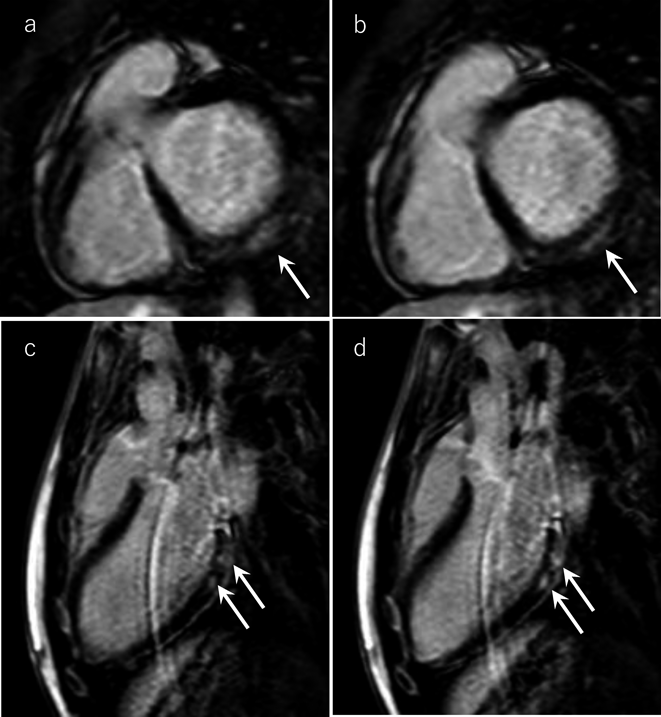

Fig. 1 Examinations on admission

a: Chest X-ray shows no abnormal findings such as no cardiomegaly, pulmonary congestion, or pleural effusion. b: 12-lead Electrocardiogram shows no abnormal findings such as ST-T change or abnormal Q.

入院時検査所見

血液検査でトロポニンI 16,001.2 pg/mL,CK/CK-MB 592/72 U/Lと心筋逸脱酵素は高値であり,CRP 1.90 mg/dLと炎症反応の軽度の高値を認めた.鼻腔SARS-CoV-2 PCR検査は陰性であった(Table 1).胸部単純X線撮影(Fig. 1a)では異常所見を認めなかった.12誘導心電図検査(Fig. 1b)ではV6誘導で基準範囲内の0.1 mV未満のST上昇があった.心臓超音波検査では心収縮は良好でejection fraction 62%, global longitudinal strain(四腔像−20.5%,二腔像−16.2%,三腔像−17.9%)も低下を認めなかった.有意な弁逆流や心嚢水の貯留は認めなかった.